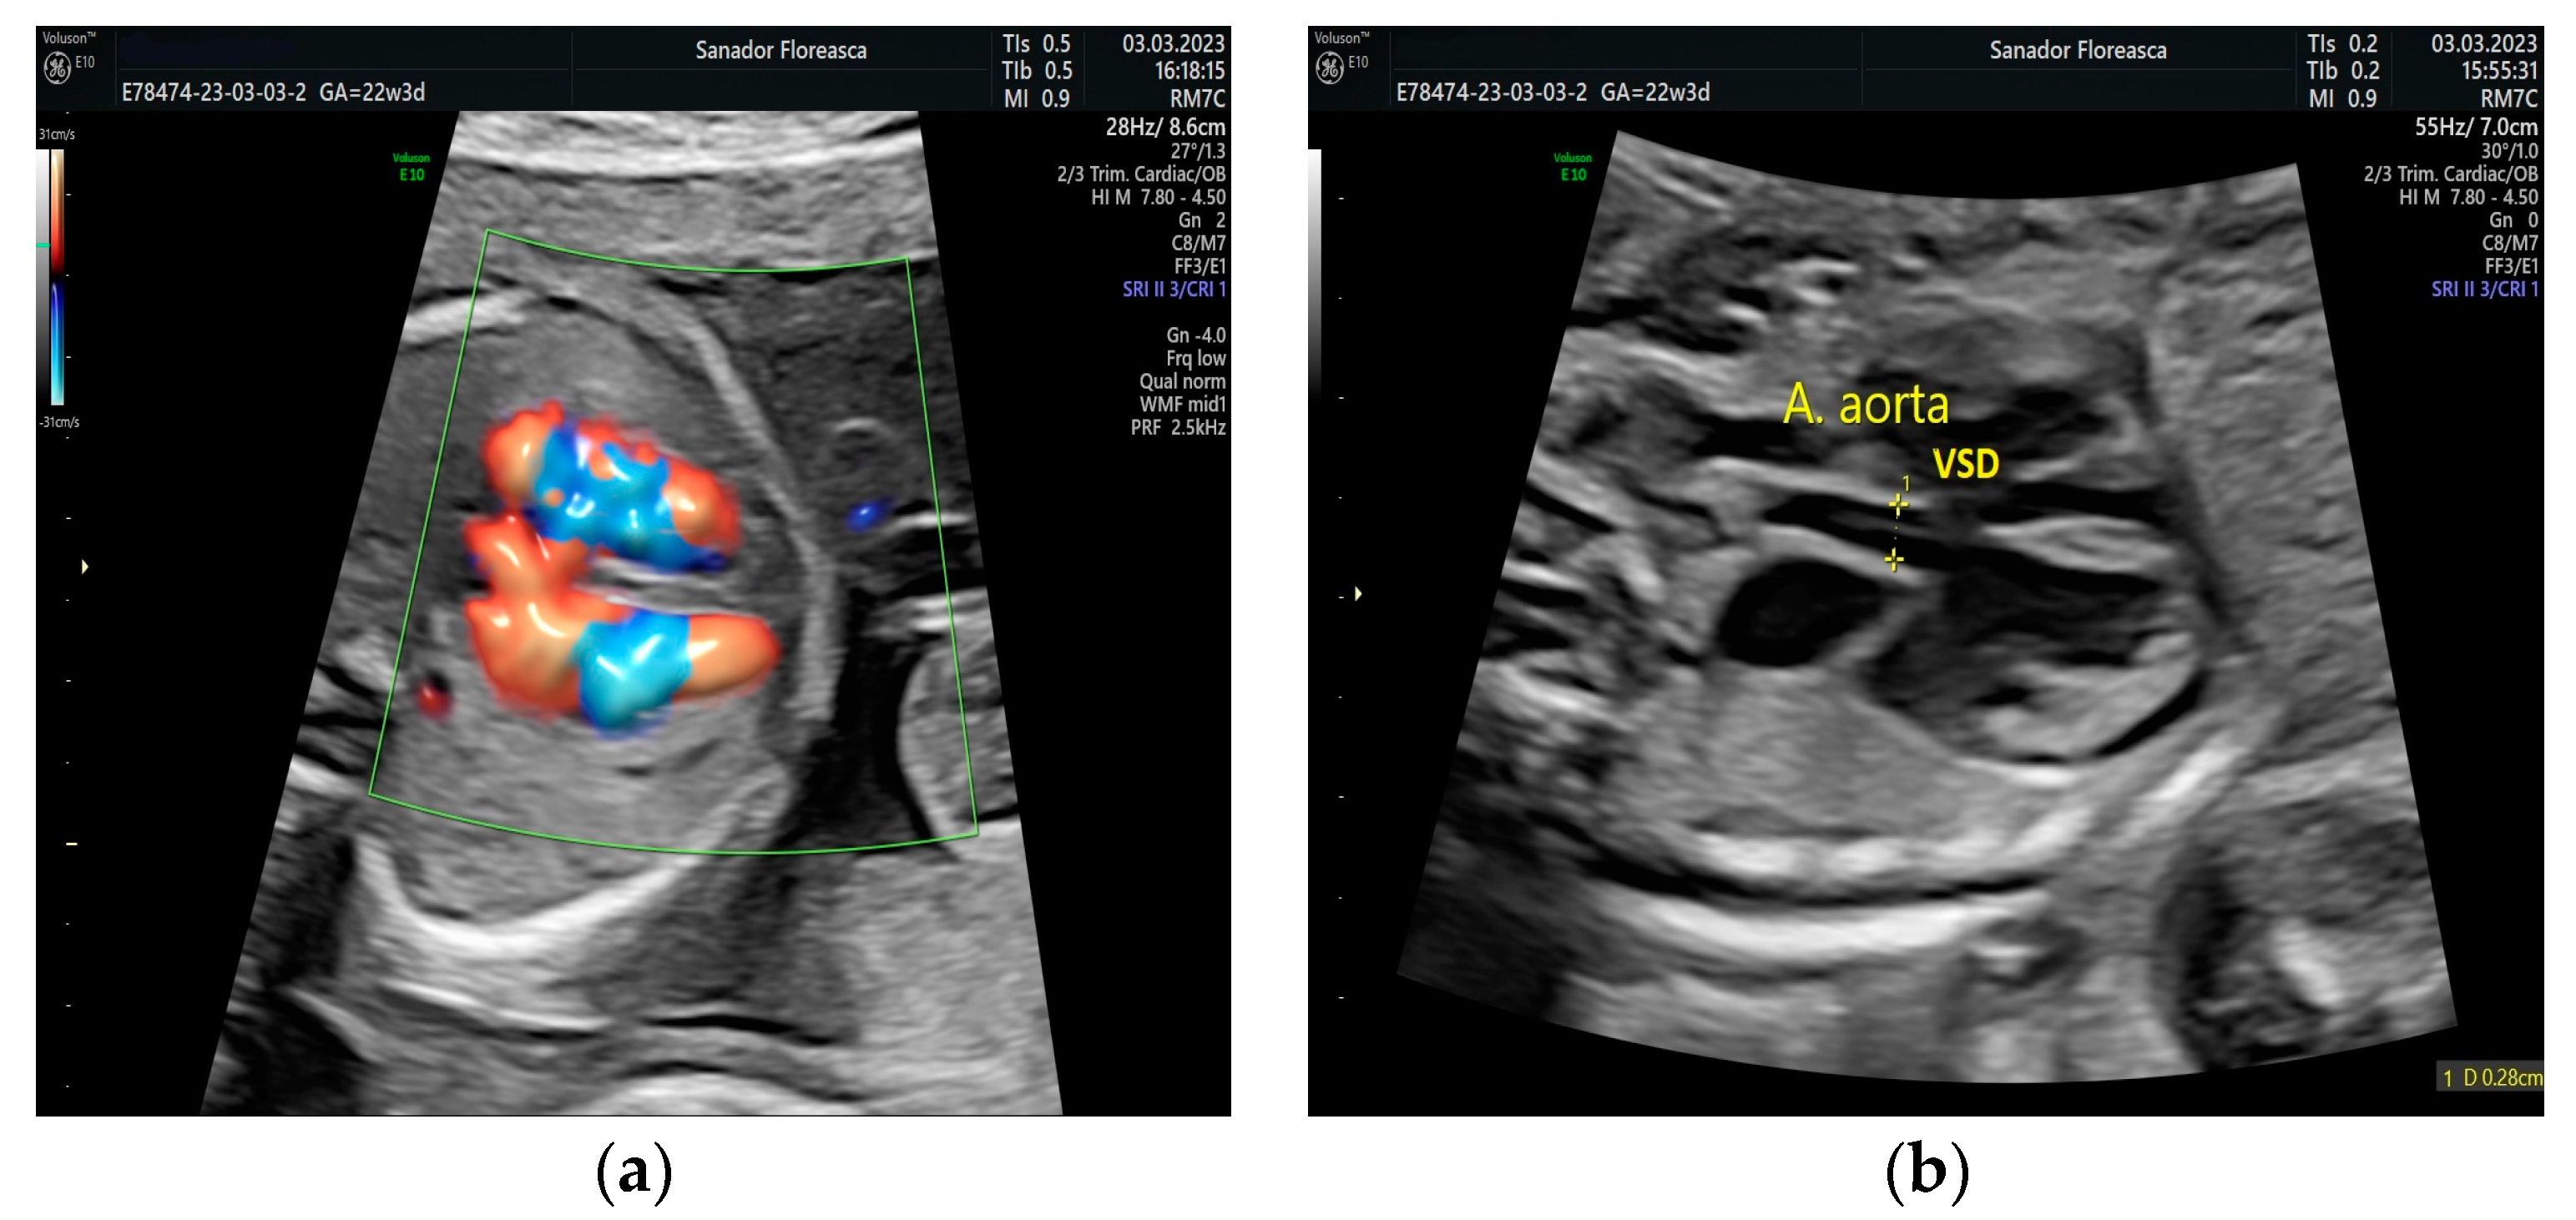

The four- chamber view showed a slightly ventricular disproportion with a narrow left ventricle when compared to the right ventricle, similar to findings in fetuses with aortic coarctation and the ventricular septal defect. The five-chamber view shows a VSD and a small descending aorta (

Figure 1).